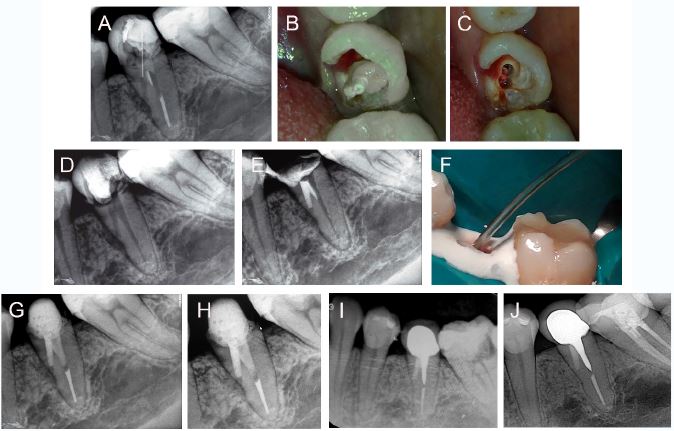

A symptomatic 43-year-old female patient without non-contributory medical history was evaluated at the endodontics department of the Central Hospital of the Peruvian Air Force.

The dental history included a root canal treatment and post placement in the second mandibular premolar (FDI 35 tooth) 3 months ago, a temporary restoration and spontaneous pain in the left mandibular area. The clinical examination showed that there was sensitivity to percussion; however, there was not extraoral or intraoral swelling. The inadequate adaptation of the provisional restoration allowed the leakage of oral fluids into the tooth. The radiographic examination revealed radiopaque line compatible with fiber post, which perforated the middle third of the root, as well as bone loss adjacent to the perforation site.

The diagnosis was previously treated and symptomatic apical periodontitis, so the non- surgical endodontic treatment, including the removal of the fiber post and sealing the perforation was recommended. The patient consented to perform the procedures.

The local anesthesia was administered by oral infiltration of 2% lidocaine with 1: 100,000 adrenaline (Alphacaine). After absolute isolation of the tooth, the fiber post was removed using an ultrasonic tip (E12, Helse Ultrasonic) coupled to an ultrasonic device (MiniEndo, Kerr Endodontics), which allowed an easy removal with a tweezer. A non-bleeding large perforation, with approximately 2-3mm in diameter, was identified and provisionally sealed with polytetrafluoroethylene (Teflon) tape to allow retreatment. The filling material was removed using the Mtwo retreatment system (VDW, Munich, Germany) using an R25.05 file complemented with Mtwo system (VDW) up to 40.04 file. The irrigation protocol was performed using 2.5% sodium hypochlorite (NaOCl) using a 27G side-vented needle (Endo-Eze Irrigator Tip, Ultradent Products). Once removed the Teflon, a calcium hydroxide dressing was placed in the canal and perforation for 15 days. In the second session, it was observed that the coronary remnant of the tooth had fractured; however, without compromising the sealing of the provisional restoration or the sufficient coronary remnant for the restoration, which allowed to continue the treatment. The calcium hydroxide was removed from the canal, leaving the residual paste in the perforation to act as a matrix for the placement of white MTA Angelus (Angelus) repair material, which was placed using an MTA Applicator (Angelus). The canal was obturated using gutta-percha points and AH Plus sealer (Dentsply DeTrey) using the continuous wave technique. A fiber post was placed immediately, and subsequently, a crown. The 6-month follow-up showed a favorable evolution. The 2-year follow-up showed that another colleague placed a metal post and a metal-ceramic crown.

Although with different prosthetic treatment, the 6-year follow-up showed a favorable evolution and bone neo-formation at the perforation site (figure 2).